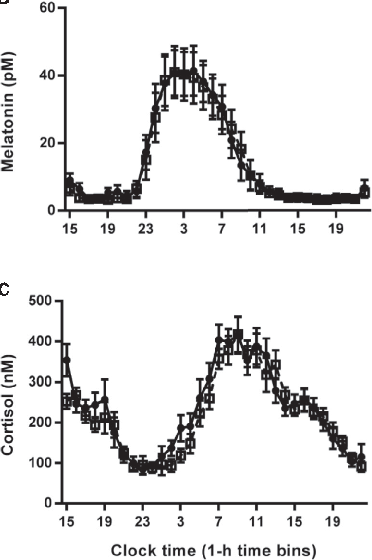

Circadian rhythm regulation involves a complex interplay between the central clock in the suprachiasmatic nuclei and peripheral oscillators throughout the body. Melatonin serves as the primary hormonal signal conveying darkness information to these systems.

Hormonal response profiles to standardized meals are compared between normal and delayed meal timing conditions, revealing shifts in metabolic hormone rhythms.

Core body temperature rhythms are displayed across experimental conditions, demonstrating that meal timing shifts selectively affect peripheral but not central circadian markers.